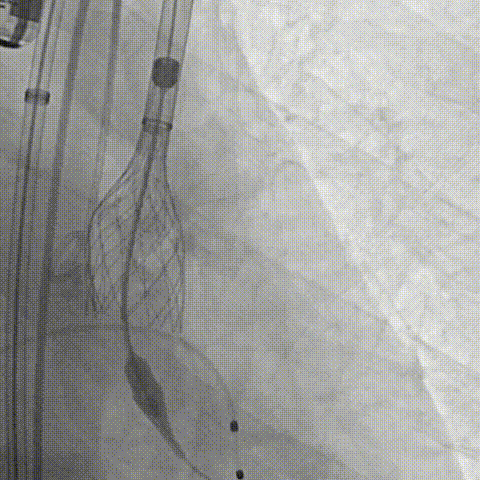

周达新教授 复旦大学附属中山医院 共识引路,干瓣启新,共赴临床解决方案:当前,结构性心脏病的介入治疗已迈入微创化、精准化的新时代。技术的革新、创新器械的上市,都是我们中国技术领跑的印证,《专家共识》的应运而生是中国医生对于行业“规范化”的践行,让治疗更精准、让医者更贴近“以患者为中心”的医疗本质。 潘文志教授 复旦大学附属中山医院 严谨求真重思考 创新临床互验证:在医学的漫长征途中,新器械的突破与严谨的临床研究是两大核心驱动力。拥抱创新的同时需要严谨求证,预装干瓣作为创新器械,其即取即用的特性可以很好的适配“急诊”的场景,此外,国产创新不是简单的复制,干瓣的瓣叶质地不是字面意思“干”的,而具“曲柔性”。所以,需要多看多测,才能全面了解一款产品。《经导管心脏瓣膜治疗术》的问世也是凝结着我们带着临床思维思考的结晶的“独家秘笈”,希望能够将“来时的路”变成未来行业同行者的“高效学习之路”! 患者病史 多病共存陷困境,主动脉瓣狭窄成 “首要威胁” 现病史:患者反复活动后胸闷2年余,无胸痛、心悸,无头晕、晕厥等不适,未予重视。患者轻微体力活动(快走、爬楼梯)即胸闷气促,静息及夜间无不适,无咳嗽、心悸等症状。为进一步诊疗收入我科,患病以来精神、食欲、睡眠、二便及体重均正常。 既往史: 2025年5月7日因小便不畅至外院住院病理穿刺确诊前列腺癌,期间检查心超提示主动脉瓣钙化伴重度狭窄,遂暂缓前列腺手术。2025年05月30日至我院就诊。 2025年5月20日开始服用比卡鲁胺片。患者血脂异常,长期服用丹参滴丸,麝香保心丸,心通颗拉。 手术史外伤史:10年前行肺手术,具体不详。否认外伤史。 入院检查 心电图提示:窦性心动过缓;ST-T改变; 心超显示:主动脉瓣钙化伴重度狭窄及轻度反流,Vmax 4.8m/s、PGmax 93mmHg、PGmean 47mmHg;左房增大,左室壁增厚。 冠状动脉CT造影:左前降支中段浅表心肌桥,主动脉瓣增厚伴重度钙化,主动脉粥样硬化。 术前CT 三叶瓣,中度钙化,主动脉根部直径25.4mm,LVOT直径23.5mm 双侧冠脉开口高度尚可,瓦氏窦尚可,ST尚可,升主尚可,冠脉风险小;中度钙化,心脏角度39.2°;心腔内径可,左室壁增厚。 外周走行尚可,全主动脉存在散在钙化,右侧穿刺点需避开钙化,血管内径可,血管内壁存在纤维增厚。 手术策略:右侧股动脉为主入路,使用20F大鞘;20球囊预扩,植入AV29瓣膜; 手术过程 主动脉根部造影 输送系统柔顺过弓 定位 缓慢释放瓣膜 造影观察 稳定脱钩 最终造影性钙位置良好,轻微瓣周漏 术后超声:轻度瓣周漏,术后平均压差11mmHg 出院前超声:平均压差11mmHg 在多基础疾病患者日益增多的当下,该病例也为临床提供重要启示:针对合并肿瘤、既往手术史的复杂瓣膜病患者,需通过多学科协作(心内科、肿瘤科、麻醉科等)全面评估病情,结合精准影像技术与适配器械,制定个体化手术方案,才能在保障安全的同时,实现最优疗效。 作为中国结构性心脏病领域的标杆学术活动,中国结构周 2025为这类高水平临床病例提供了交流平台,助力推动我国结构性心脏病诊疗技术持续创新,让更多复杂瓣膜病患者受益于精准医疗方案。 ProStyle A®预装干瓣——助力临床最优化解决方案: 轻松过弓,精准可控:该病例全主动脉存在散在钙化,右侧穿刺点需避开钙化,ProStyle A®较细的尺寸+柔顺的输送系统通过性能得到了很好的验证; 平稳释放:平衡的径向支撑力降低了释放过程中的张力,流入端小锥角设计能够迅速锚定贴边; 预装干瓣 便捷顺安:金仕生物专利抗钙化技术运用纳米技术去除组织内的细胞碎片和磷脂,封闭游离醛基,从根本上阻断了瓣膜钙化的多项因素,显著提升了瓣膜的耐久性;同时,相比较传统戊二醛保存方式,干式存储最大限度的保留心包的亲水亲油平衡,还原组织天然曲柔性,进一步保障了瓣叶开合,保证长期耐久性; 专家简介 葛均波 复旦大学附属中山医院(点击查看专家详细简历) 周达新 复旦大学附属中山医院(点击查看专家详细简历) 潘文志 复旦大学附属中山医院(点击查看专家详细简历) · END ·